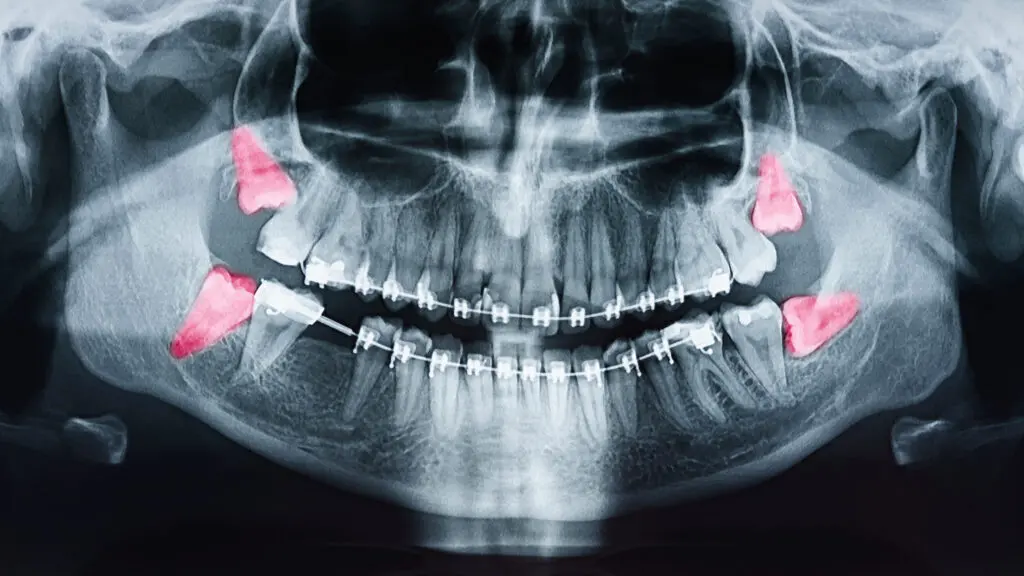

Zuby moudrosti se sice stále vyvíjejí (začínají se tvořit už kolem 7. až 10. roku života!), ale často pro ně v našich zmenšených čelistech prostě není místo. A co se stane, když se zub snaží prořezat, ale nemůže?

- Zůstane uvězněný v dásni: Tomu se říká impaktovaný zub. Může to bolet, způsobovat záněty a poškozovat okolní zuby.

- Vyroste křivě: Může tlačit na ostatní zuby, způsobovat jejich posun a opět – bolest a záněty.

- Prořeže se jen částečně: Kolem takového zubu se snadno hromadí bakterie a zbytky jídla, což vede k zánětům dásní a kazům.

Pokud máte tyto příznaky, je čas navštívit zubaře. Ten vám udělá rentgen a zjistí, jak na tom vaše zuby moudrosti jsou a jestli je potřeba je vytrhnout.

- Když jsou impaktované: Tedy když nemohou prořezat a zůstávají uvězněné v dásni.

- Když rostou křivě: A tlačí na ostatní zuby.

- Když způsobují opakované záněty dásní nebo kazy.

- Když je pro vás obtížné je čistit: Kvůli jejich špatné poloze.